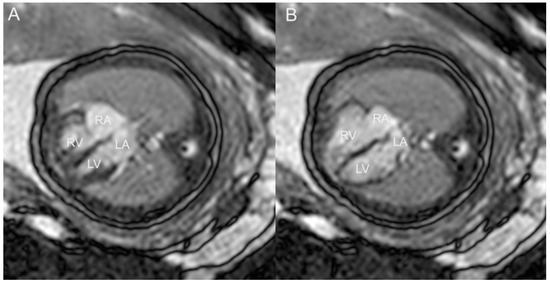

- Liu, K.; Zhu, M.; Zhang, Y.Q.; Chen, L.J.; Dong, S.Z. Utility of fetal cardiac magnetic resonance imaging in assessing the cardiac axis in fetuses with congenital heart disease. Pediatr. Radiol. 2023, 53, 910–919. [Google Scholar] [CrossRef]